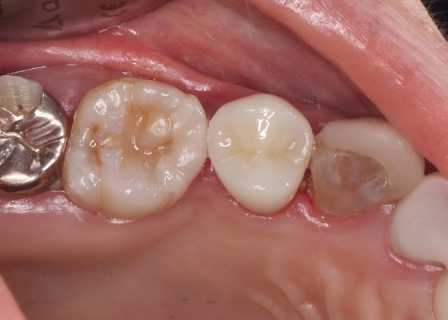

| 患者 | 60代女性 |

| 主訴 | 「噛むと痛みがあり、違和感もある」とご相談いただきました。 |

| 診断 | 拝見したところ、右上の歯に深い虫歯が見つかりました。

レントゲン撮影で詳しく検査した結果、虫歯が神経まで進行しており、歯根の先に黒い影が確認できます。 このまま放置すると、炎症が広がって歯を支える骨が溶けるおそれがあるため、早急に治療をする必要があると診断しました。 |

| 行ったご提案・治療内容 | 患者様は、歯をできるだけ残したいと希望されています。 そのため、感染した神経を取り除いて歯根内部を清掃・消毒する「根管治療」を行い、歯全体を覆う被せ物を装着する方法を提案し、同意いただきました。 メリット デメリット まず、根管治療で神経を慎重に取り除き、根管内の清掃と消毒を行います。 次に、歯を保護するための被せ物「ジルコニアクラウン」を装着します。 最後に、痛みや違和感がないか、問題なく噛むことができるかを確認し、治療を終了しています。 |

| 治療期間 | 約1ヶ月 |

| 費用 | 約260,000円 (根管治療、ジルコニアクラウン) |

治療前

治療中

治療後